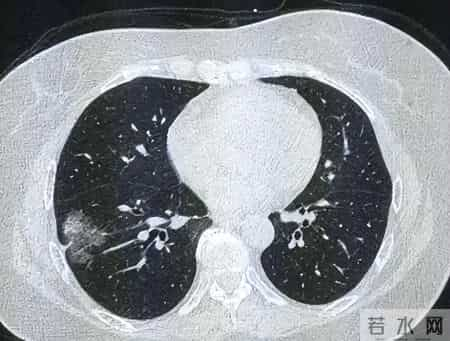

肺结节,指的是肺部直径小于3厘米的团块,其实可能是炎症、钙化、感染,也可能是良性肿瘤,更可能是早期恶性肿瘤。

根据北京协和医院肺科2023年随访数据,超过5%的肺结节在1年内可进展为恶性肿瘤。如果是某些高风险结节,生长、恶变的速度远远快于一般人的想象。

即使最初影像报告显示“小”“边界清”,也不可掉以轻心。权威指南强调,随诊和动态复查,是阻止小结节变大祸的关键一步。但遗憾的是,现实生活里,像老孙这样疏忽随访、等症状明显时才重视,已经太晚。

值得注意的是,肺结节“变坏”没有早期特异症状,很多人在咳嗽、胸闷等症状出现时,其实已经进入了进展期或晚期阶段,失去了最佳治疗窗口。